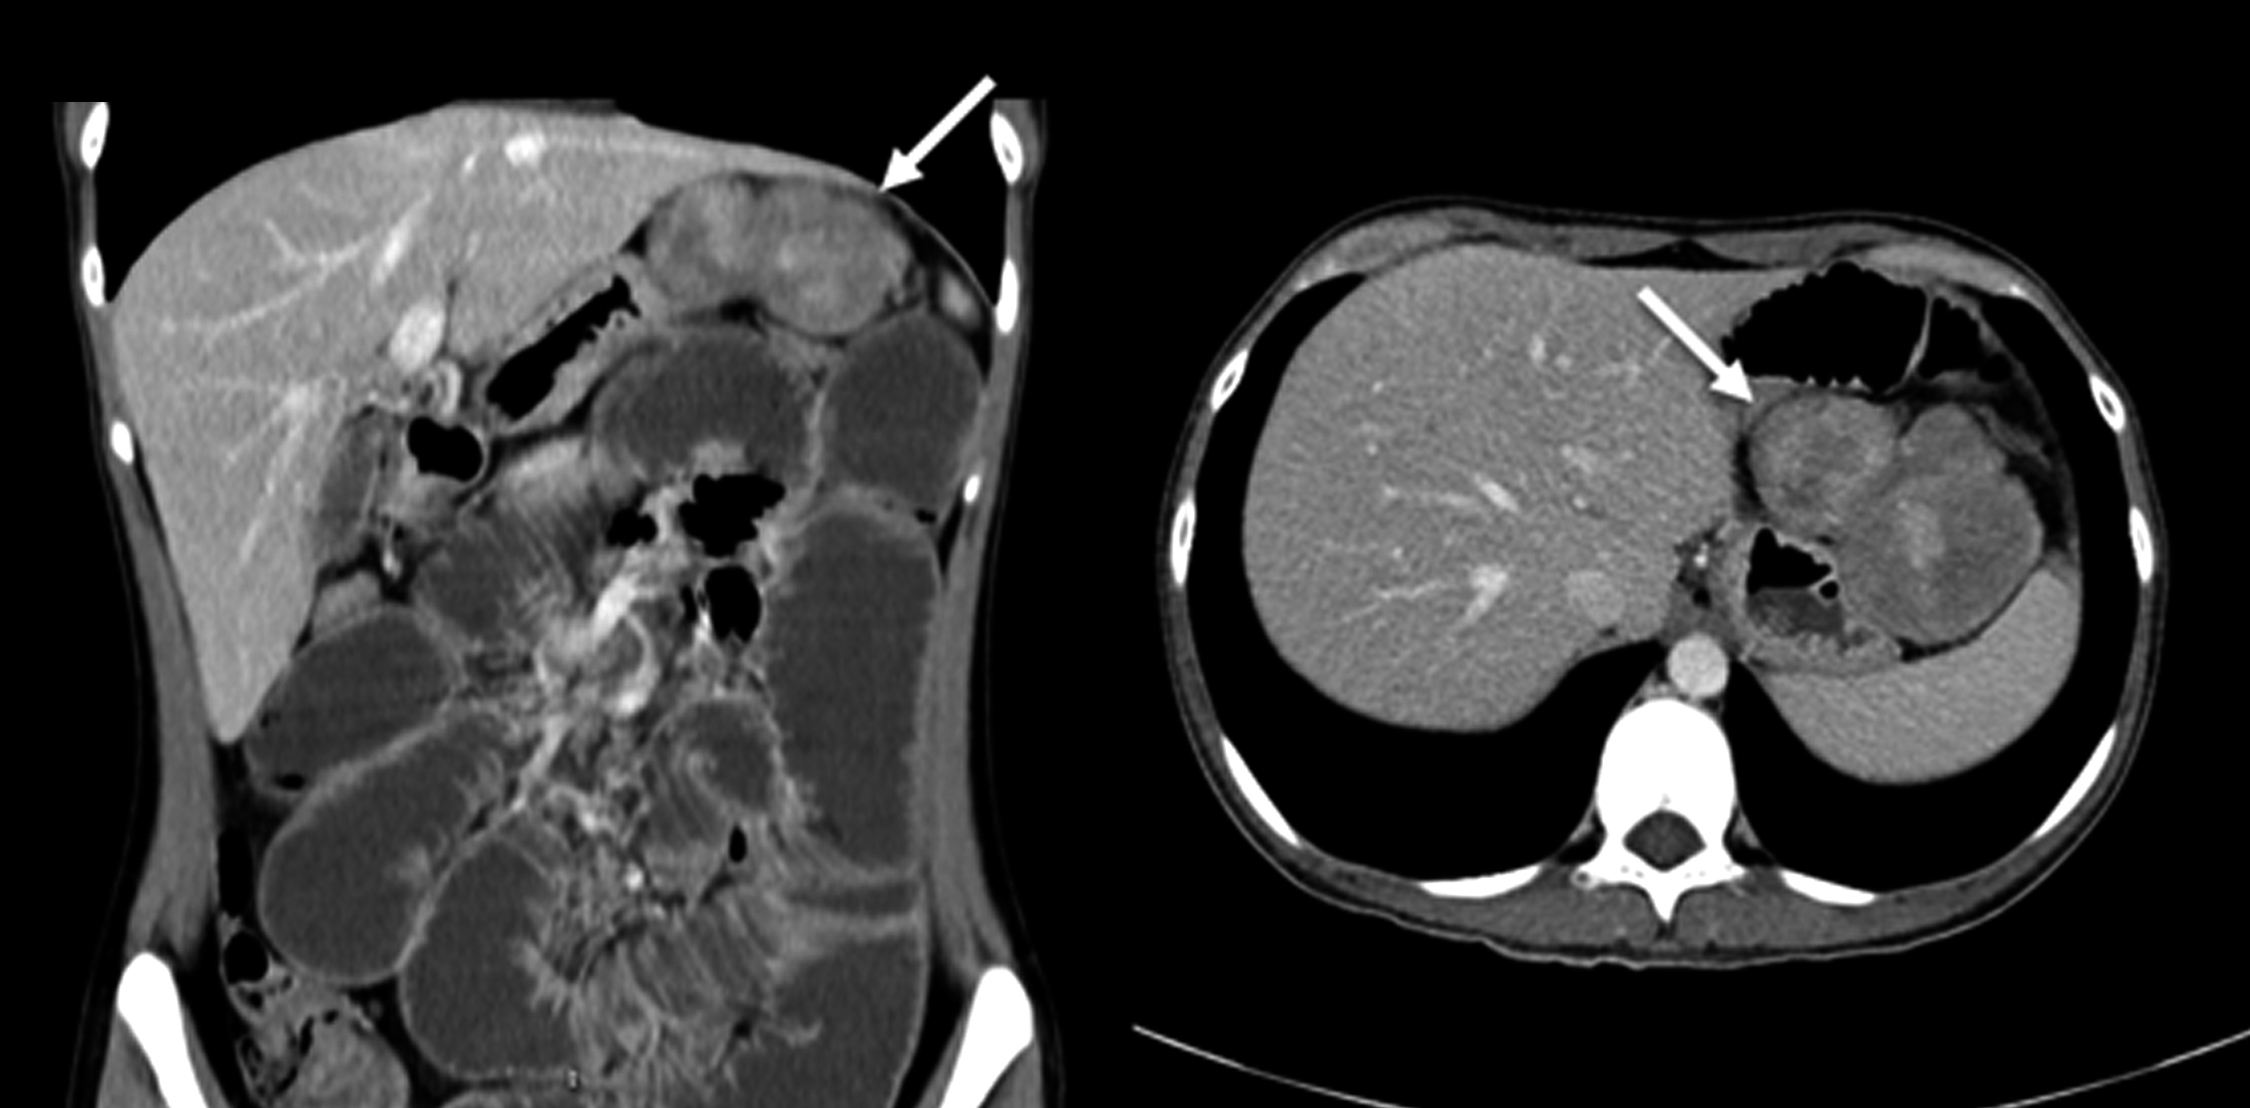

Se realiza TC de abdomen y pelvis sin y con medio de contraste intravenoso. Se identifica a nivel de flanco izquierdo masa sólida, bilobulada, de bordes lisos, bien definida, que mide 80 x 50 x 50 mm de diámetro en sus ejes L, T, AP respectivamente, con realce heterogéneo con el medio de contraste. Se encuentra por delante del colon descendente y por fuera de las asas delgadas e impresiona tener plano de separación con dichas estructuras, por lo que se interpreta que probablemente corresponda a una masa intraperitoneal (Figura 6).

Figura 6

TC de abdomen: corte axial previo al contraste donde se evidencia a nivel del flanco izquierdo masa sólida bilobulada con bordes lisos (a), que muestra realce heterogéneo luego de la administración de contraste (b) (flechas)

Se realiza otra TC de abdomen y pelvis, sin y con medio de contraste intravenoso. Se identifica masa sólida de similares características que en la TC previa, pero actualmente localizada en hipocondrio izquierdo, subhepática, adyacente a la curvatura gástrica mayor y asas delgadas. Se observan asas delgadas distendidas con niveles hidroaéreos, con zona de transición a nivel pelviano. Se plantea oclusión por bridas. (Figura 7)

Figura 7

TC de abdomen: reconstrucción en plano coronal (a) y corte axial (b), donde se observa, seis meses después de la primera TC, la misma masa sólida pero actualmente ubicada en el hipocondrio izquierdo (flechas) que asocia dilatación de asas delgadas.